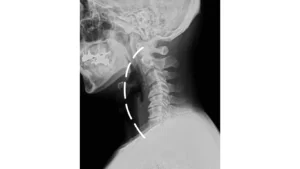

①問診・レントゲン分析

時間をかけて丁寧な問診を行い患部がどのように痛むか、どのようにして問題が起きたか、日常の姿勢等、多面的に伺い要因を限定していきます。基本的にレントゲン分析を行いますが、必要であれば更にCTスキャン・MRI等を参考にします。